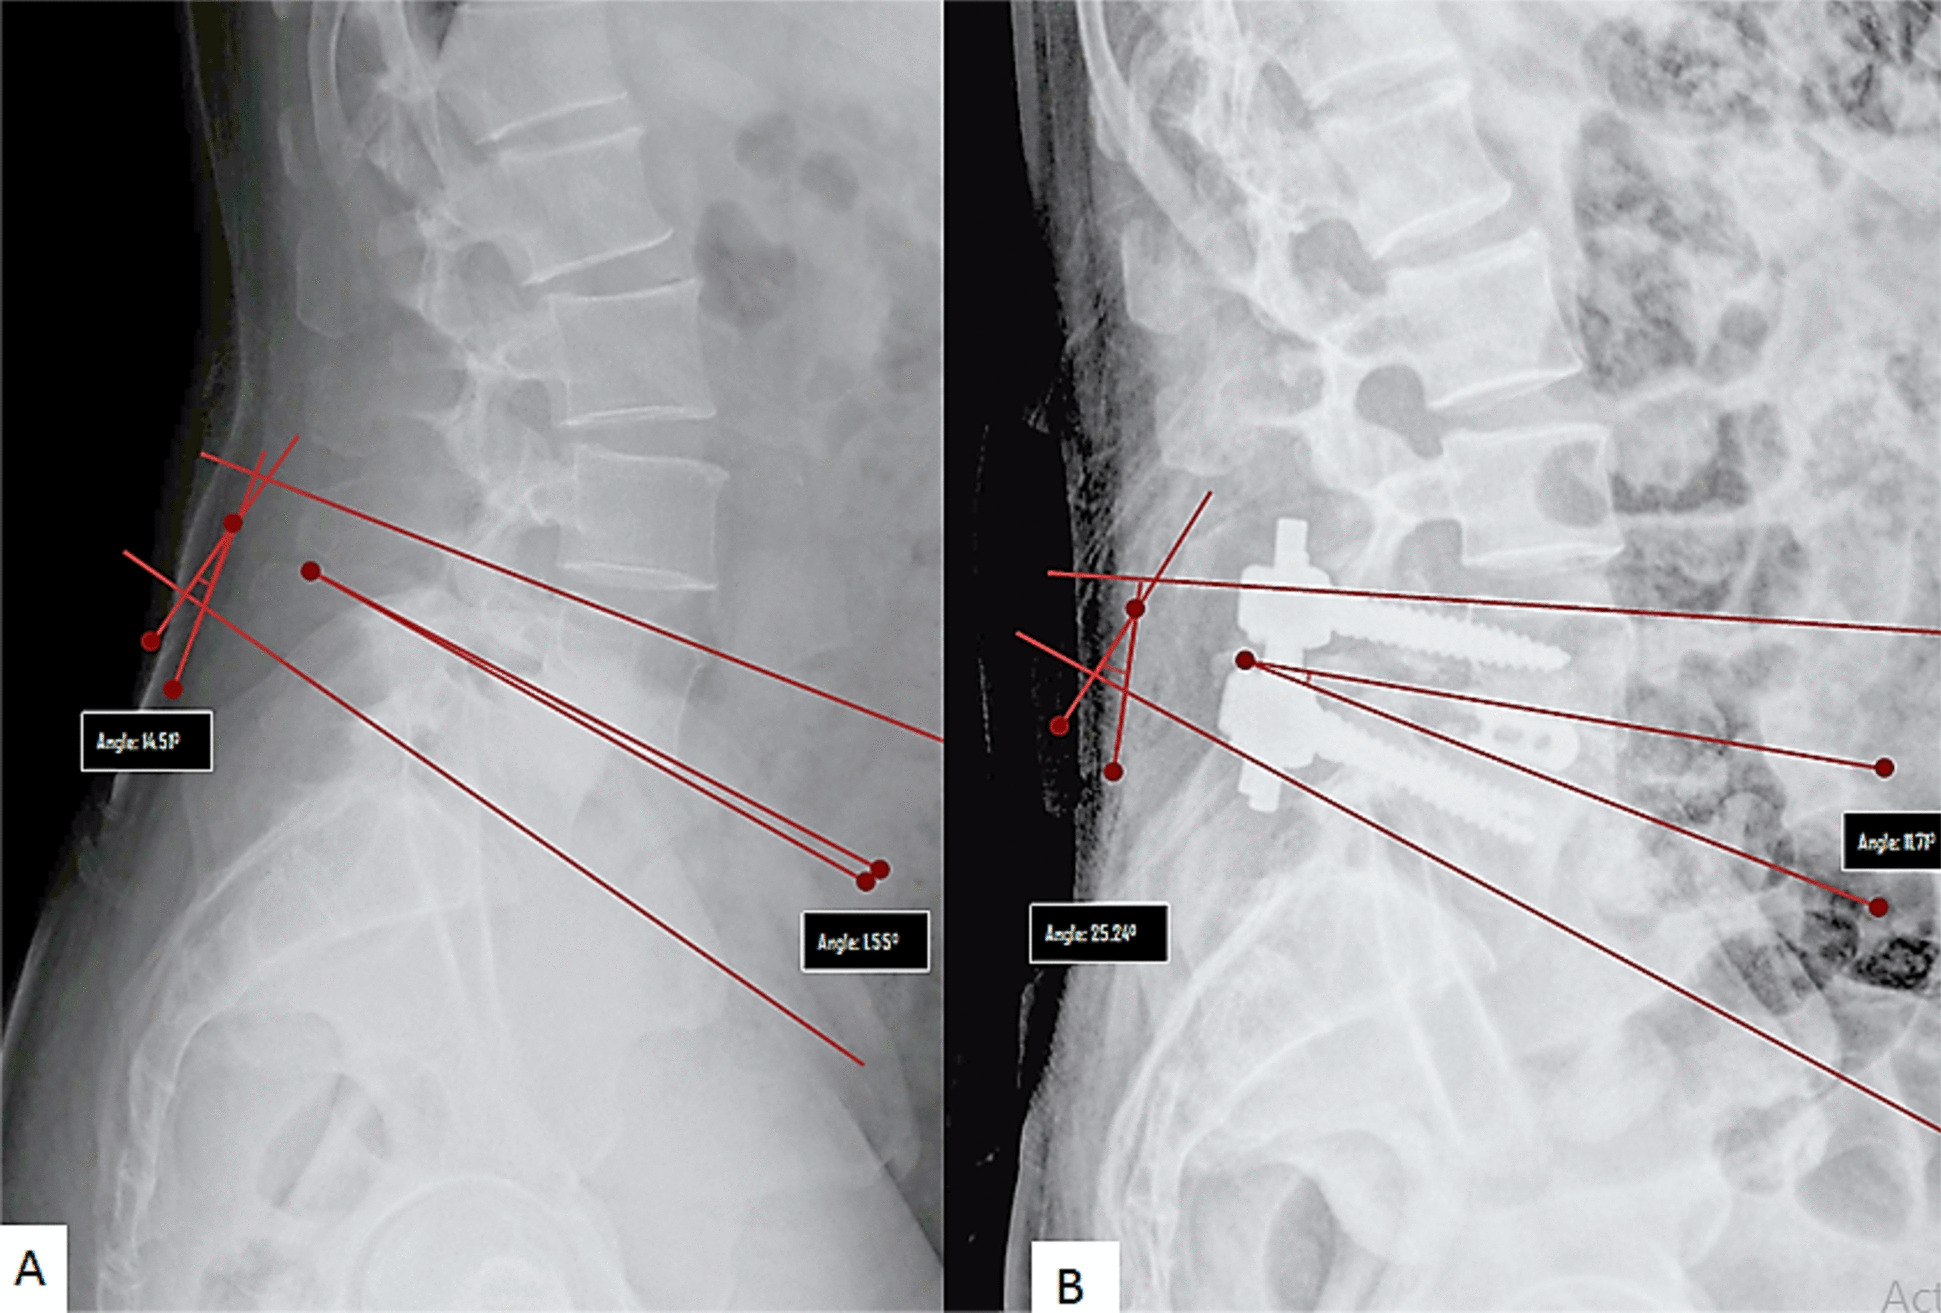

Methods: A single-centre, retrospective study on 74 patients with degenerative and lytic lumbar spondylolisthesis who underwent single level transforaminal lumbar interbody fusion (TLIF) surgery between August 2020 and July 2022 with a minimum follow up of 1 year. Radiographic measures included disc angle(DA), SLL, lumbar lordosis(LL), anterior/posterior disc height(ADH/PDH), spondylolisthesis percentage(SP) and pelvic parameters like pelvic incidence(PI), pelvic tilt(PT) and sacral slope(SS). Surgery-related measures included cage position, spondylolisthesis reduction rate, rod contouring and disc height restoration rate(DHRR). For analysis, change in SLL ≥ 8° indicated increased segmental lumbar lordosis(ISLL), and < 8° indicated unincreased segmental lumbar lordosis(UISLL).

Results: The mean age of the entire cohort was 42.4 years, with 76% of the patients being female. In our study 62% patients had UISLL and 38% had ISLL. In lytic listhesis group, on multivariate analysis the LL, DA, cage position were significant predictors of restoration of SLL. In degenerative listhesis, age and preoperative SP were significant factors. DHRR was the only significant predictor for restoring good PI-LL(Pelvic incidence minus Lumbar lordosis).

Conclusion: Preoperative LL, DA and intraoperative cage position emerged as significant predictive factors. Surgeons should place the cage more anteriorly, with efforts to restore disc height to maximise the restoration of SLL and to attain a good PI-LL.